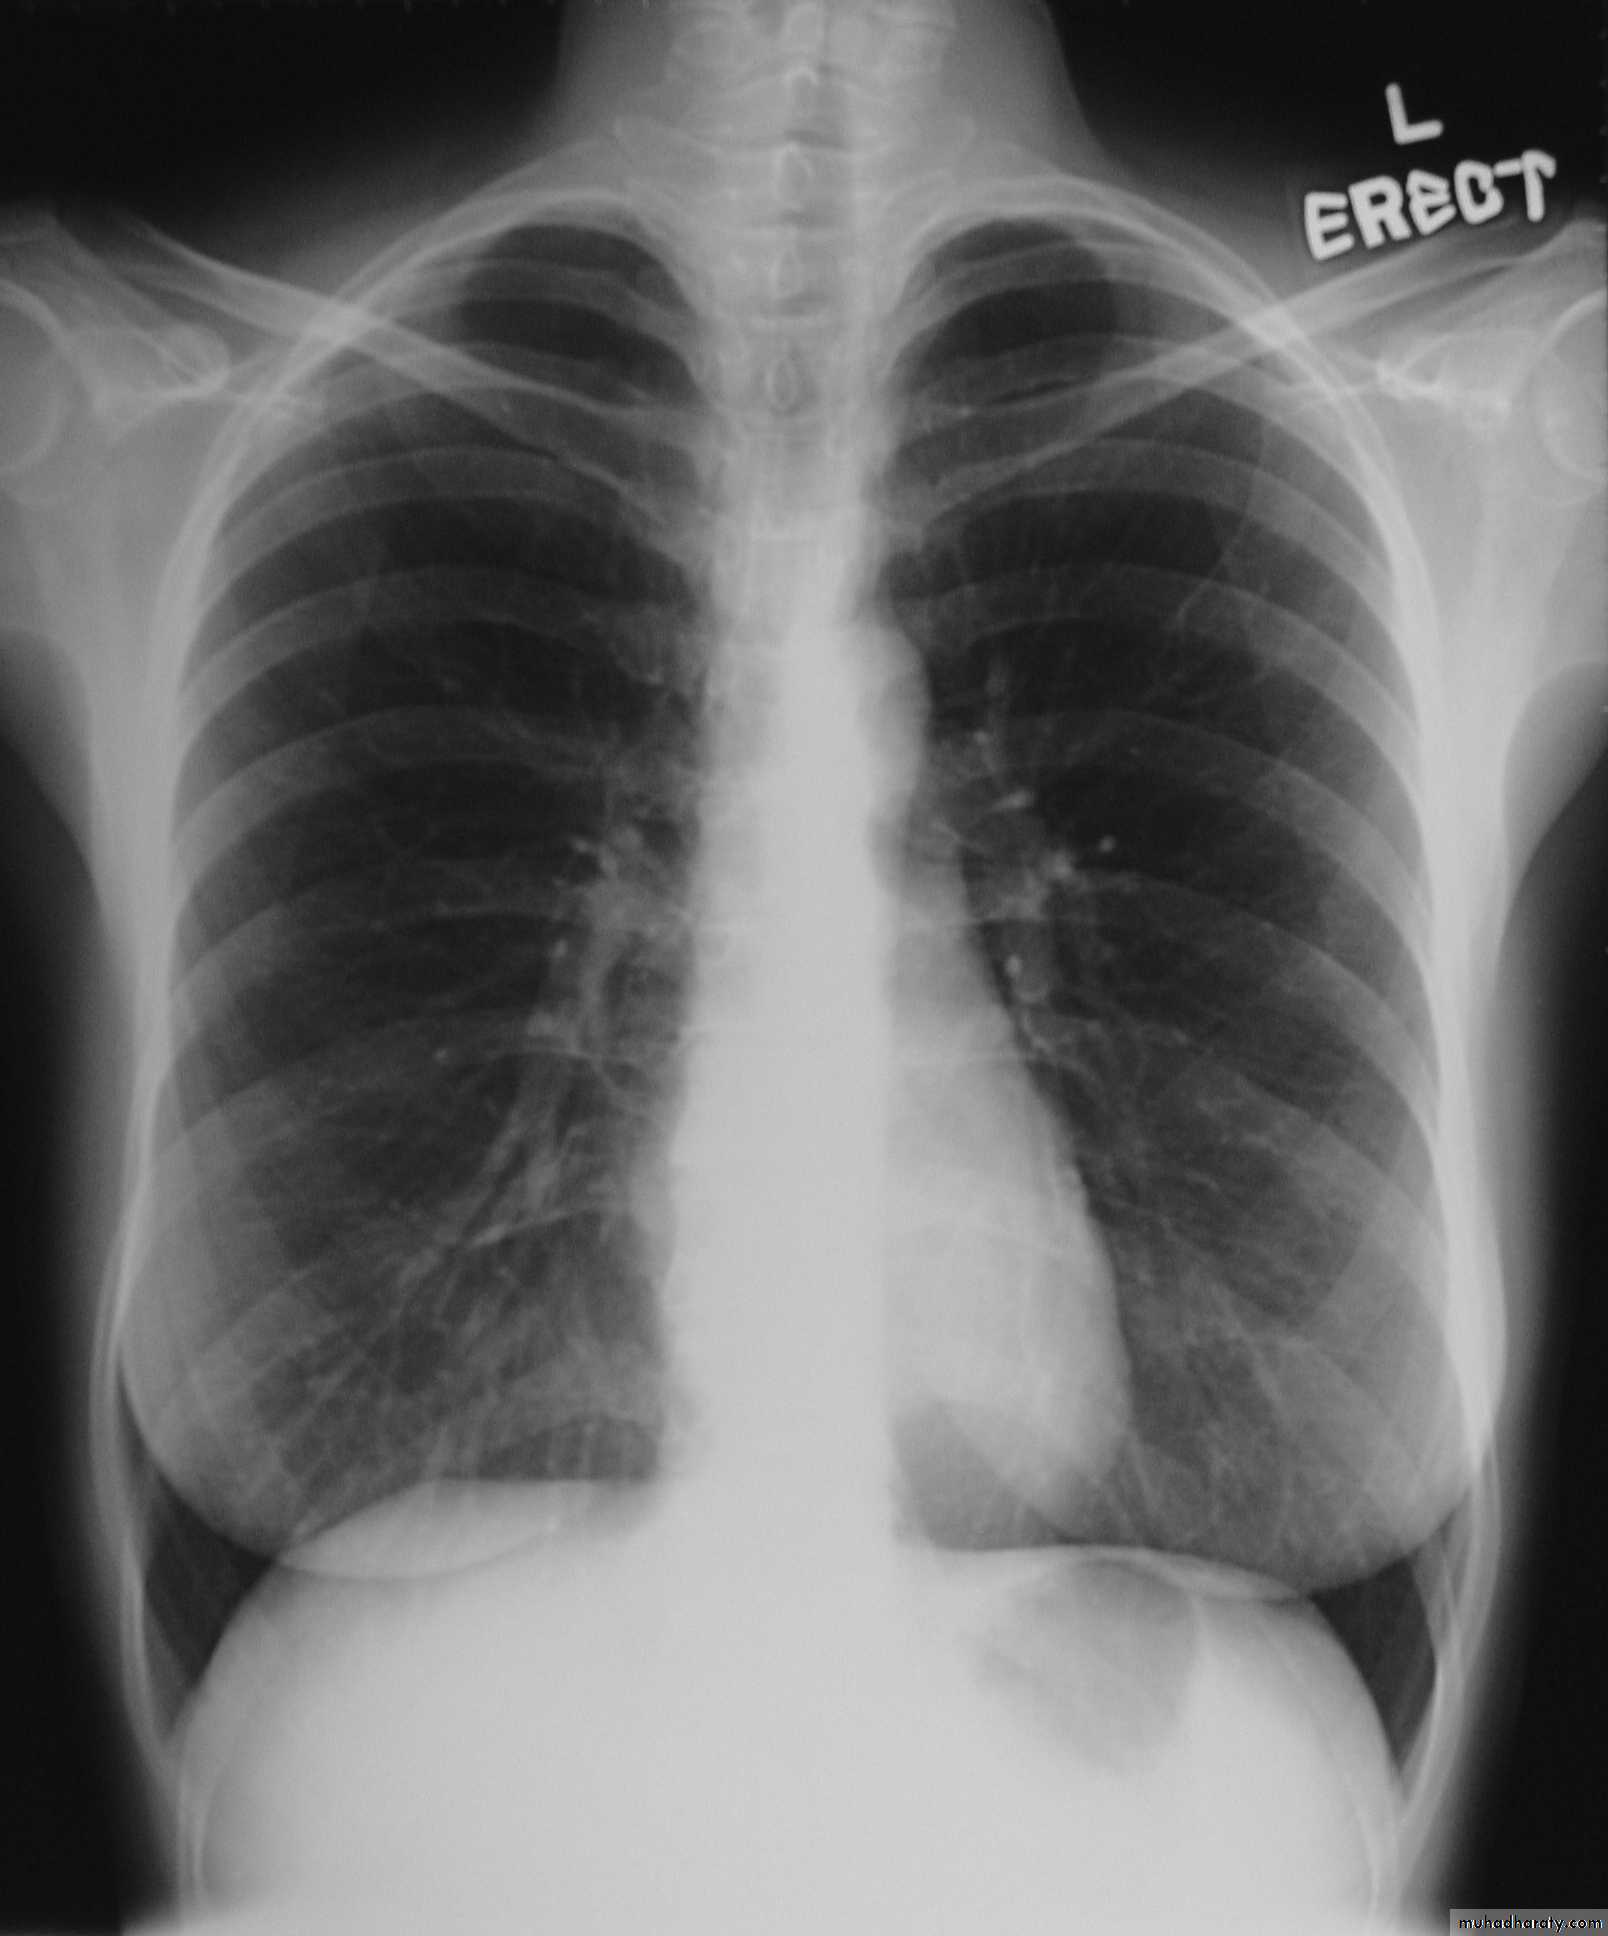

Investigations Chest X-ray; widening of the mediastinum, aspiration pneumonia.A barium swallow; tapered narrowing of the lower esophagus, esophageal body is dilated, aperistaltic and food-filled.Endoscopy; must always be carried out, carcinoma of the cardia can mimic the presentation and radiological and manometric features of achalasia ('pseudo-achalasia').Manometry; confirms the high-pressure, non-relaxing lower esophageal sphincter with poor contractility of the esophageal body.